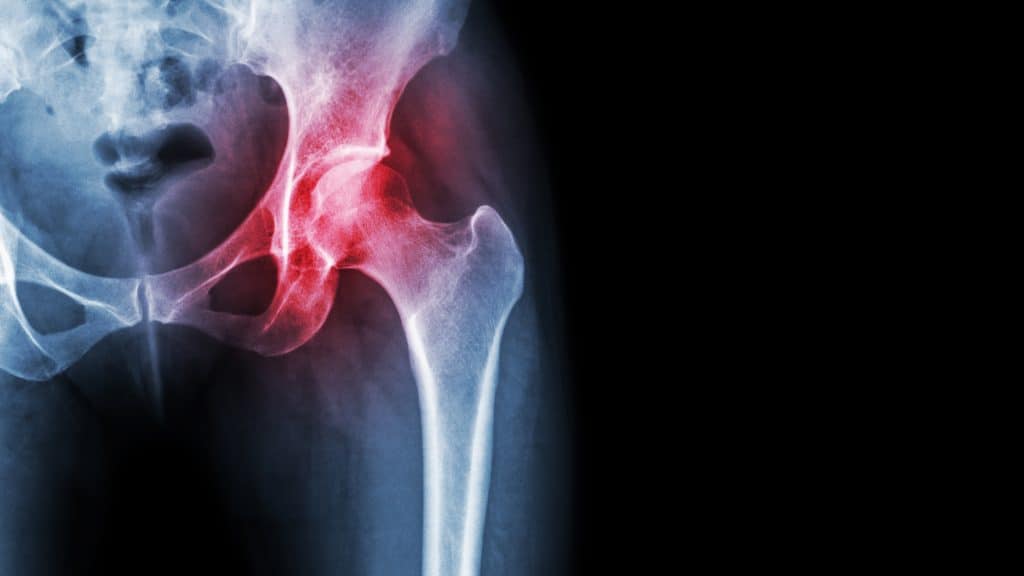

Čovjek kako stari tako se sve više povećava mogućnost pojave raznih oblika bolesti i narušenja zdravlja koje nam mogu itekako narušiti opću kvalitetu života. Jedna od takvih bolesti zasigurno je osteoartritis kuka. Znate li o čemu se radi? Što uzrokuje ovu bolest, kakvi su simptomi i kako izgleda liječenje? Kažu da poznavanje bolesti jest prva pretpostavka u njezinoj prevenciji. Upravo zato ćemo u nastavku iznijeti sve korisne informacije koje se odnose na ovu bolest. Moguće da ste već osjetili bol u području kuka ali niste ni približno mogli procijeniti što tu bol uzrokuje. Moguće da je riječ o osteoartritisu kuka koji je jedan od najučestalijih razloga bolova u kuku. Osteoartritis kuka nastaje zbog razaranja hrskavice u tom zglobu što posljedično vodi do toga da se povećava trenje koštanih struktura u tom zglobu. Upravo to trenje vi osjećate kao bol. Radi se o kroničnoj i progresivnoj degenerativnoj bolesti koja je jedna od najčešćih uzroka onesposobljenosti osoba starije dobi. Uroci su većinom kombinacija životnih navika, genetike i raznih trauma.